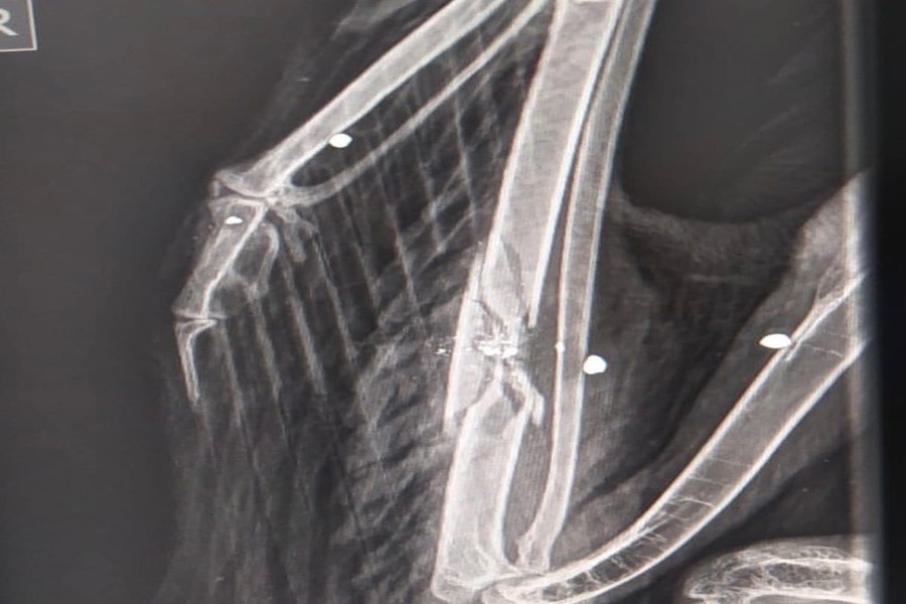

El equipo de rescate de la Corporación llegó hasta Toche, corregimiento de Ibagué, para recibir un Águila Real de Páramo de nombre científico (Geranoetus melanoleucus) la cual fue atacada con 5 perdigones.

El ave presenta fractura de ulna o cúbito del ala derecha y tiene algunos perdigones incrustados en el tejido muscular.

Cabe señalar que, según el informe de la especie silvestre se anuncia que perdió mucha sangre e ingresó al Centro de Atención y Valoración de Fauna – CAV, donde el equipo veterinario reaccionó de manera inmediata junto al Hospital Veterinario de la Universidad del Tolima, donde están haciendo todo lo posible para que evolucione de la mejor manera.